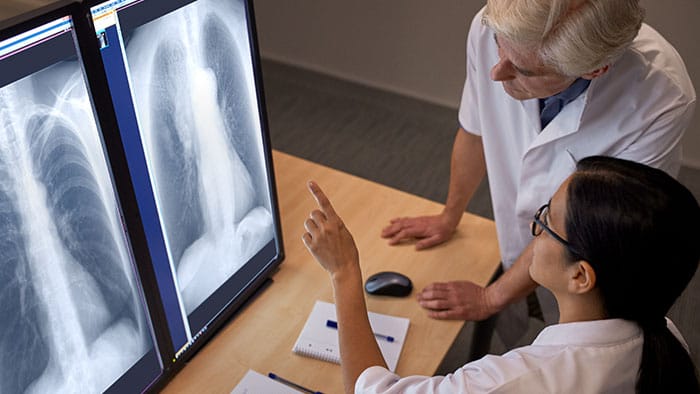

Procesamiento de imágenes de última generación

UNIQUE 2 de Philips es la última iteración de nuestro software de procesamiento de imágenes ya consolidado. Al aumentar el contraste y reducir el ruido y los artefactos, UNIQUE 2 agudiza la visualización de detalles anatómicos sutiles.

Calidad de imagen clínica uniforme para todos los tipos de anatomía.

El software de procesamiento de imágenes UNIQUE 2 ofrece imágenes excelentes para cada tipo de anatomía a través de ajustes preestablecidos y parámetros personalizados. Los ajustes preestablecidos funcionan automáticamente y se ajustan al tipo de paciente (adulto, niño o bebé, delgado u obeso) y a los requisitos del examen.

UNIQUE 2 armoniza los niveles de contraste, aportando detalles a regiones muy oscuras y muy brillantes. Es posible notar una optimización de la imagen tanto en las áreas altamente expuestas (e. j.: ápice pulmonar), como en las áreas apenas expuestas (e. j.: región retrocardíaca y parte superior del abdomen). Al centrarse en las estructuras más relevantes desde el punto de vista diagnóstico, UNIQUE 2 mejora los detalles, mientras que la impresión general sigue siendo neutral.